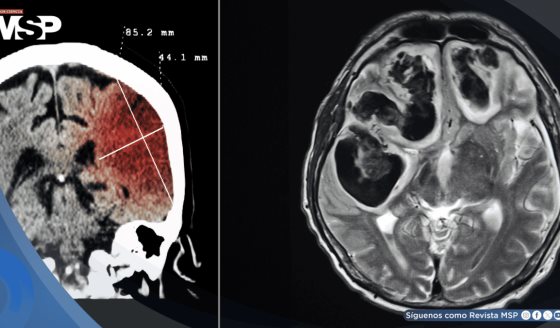

La tomografía computada, considerada una herramienta clave en el diagnóstico médico moderno, está siendo reevaluada por la comunidad científica a raíz de un estudio que alerta sobre su potencial riesgo cancerígeno.

Publicado en JAMA Internal Medicine, el análisis proyecta que más de 100.000 personas podrían desarrollar cáncer como resultado de haberse sometido a TC durante el año 2023 en Estados Unidos.

El estudio estima que, si las prácticas actuales se mantienen, unas 103.000 personas desarrollarán tumores malignos a lo largo de su vida a raíz de las exploraciones por TC realizadas en 2023. Esta cifra representa un preocupante 5 % del total de nuevos diagnósticos de cáncer anuales en Estados Unidos.